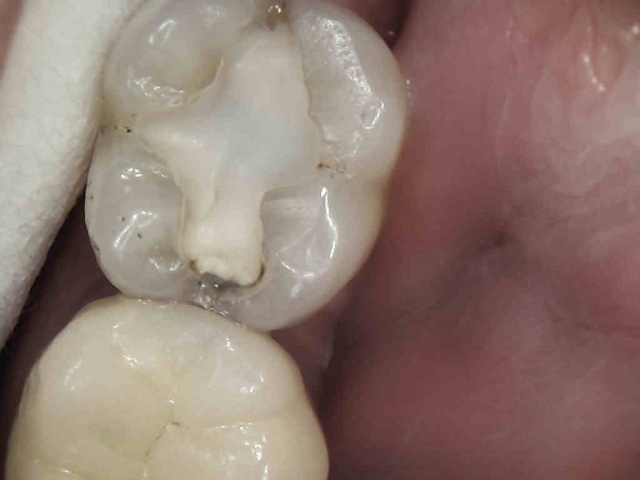

Patient 5: Tooth #18

This patient was referred from a periodontist who was going to extract #19 with socket preservation. The black and white image is deceiving, as they can be sometimes. Here, the mesial does not show a definitive lesion. It is here that the clinical examination is key. Do you examine and chase cracks? If a marginal ridge has a crack that is palpable to your explorer and is discolored, it is leaking. The photo image shows this well. The image that follows shows quite a different story than the black-and-white image. Notice the crack mid-prep is still quite prevalent.